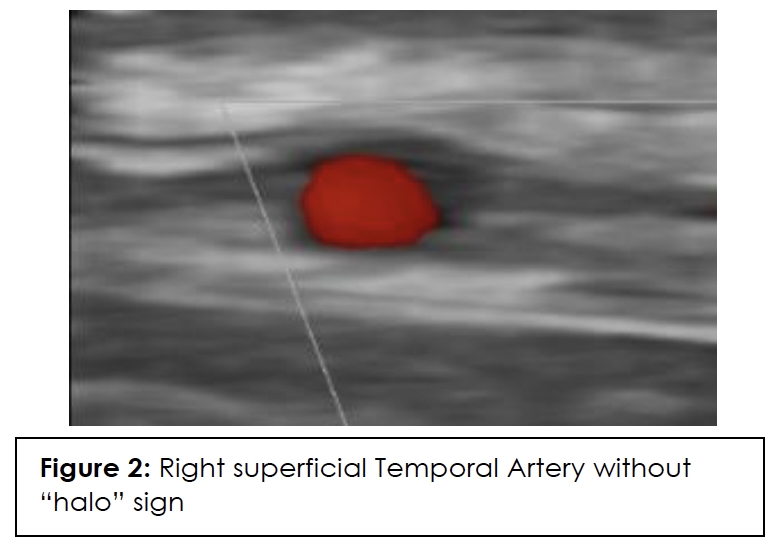

ESR, CRP, and color Doppler ultrasound (CDUS) of his temporal artery in July 2023 were negative, showing no GCA in the superficial temporal arteries. CDUS of bilateral temporal arteries demonstrated normal flow characteristics (Figures 1,2,3,4). Physical examination and temporal predominance of headache prompted obtaining the temporal artery biopsy in August 2023, which revealed healing GCA (Figure 5). The presence of myxoid change in the asymmetrically thickened intima and a residual infiltrate of mostly macrophages at the tunica intima-tunica media interface where the internal elastic lamina was absent allowed distinction of healing arteritis from age-related histopathological change, which may resemble healed giant cell arteritis. 3

In addition to laboratory results, color Doppler ultrasound (CDUS) of the temporal artery is now considered first-line for diagnosis because it has a higher sensitivity than temporal artery biopsy and is of lower cost and less invasive. The hallmark “halo sign,” visible on ultrasound, indicates inflammation of the vessel walls. Bilateral temporal “halo sign” is highly specific for GCA.36 In the 2016 TABUL study37 (a multi-center, prospective study for GCA), ultrasound had sensitivity of 54% and specificity of 81%, while temporal artery biopsy had sensitivity of 39% and specificity of 100%. Temporal artery biopsy remains the gold standard for diagnosis. The lower sensitivity of biopsy is likely due to skip lesions and prior corticosteroid treatment. Unexpectedly, our patient’s ultrasound was negative but biopsy was positive for GCA. Temporal artery abnormalities, including beading (irregular contour), prominence, tenderness, and an absent pulse, are reported to significantly increase the likelihood ratio for a positive temporal artery biopsy (TAB).38 Our patient had prominent temporal arteries on examination, giving him an increased likelihood of positive biopsy.

Ultrasound halo size abnormalities reduced after four or more days of high-dose glucocorticoid treatment. The percentage of positive biopsy results dropped significantly when patients began glucocorticoid treatment within 3 days.39 Our patient had the ultrasound performed approximately 20 days before starting the steroids, so the absence of the halo sign cannot be attributed to the steroids.